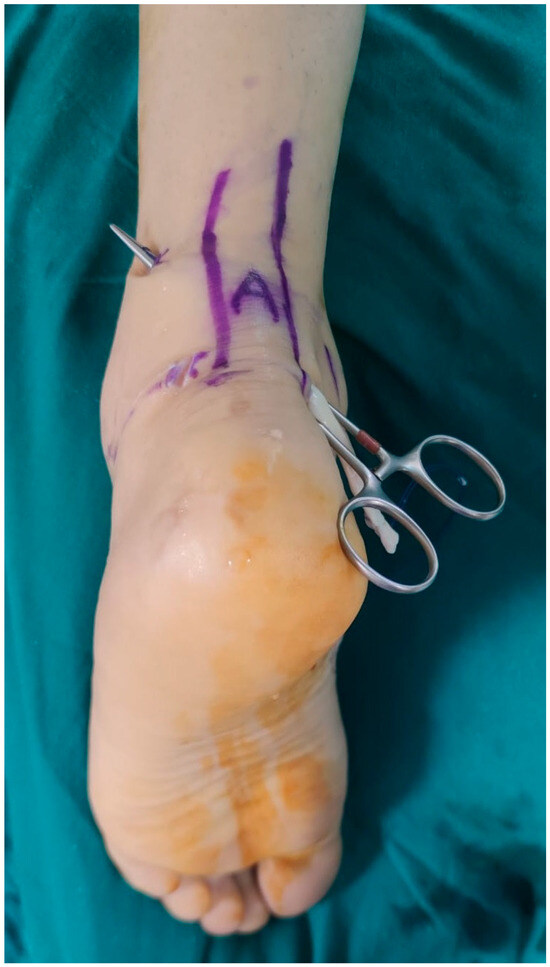

Outcomes of Lapidus Procedure Without Focused Frontal Plane Rotation of the First Metatarsal

J. Am. Podiatr. Med. Assoc. 2026, 116(3), 22; https://doi.org/10.3390/japma116030022 - 23 Apr 2026

Background: We present a retrospective radiographic analysis showcasing the ability to correct hallux valgus using the Lapidus arthrodesis without focused frontal plane rotation of the first metatarsal. Methods: A total of 33 feet in 30 patients who had undergone Lapidus arthrodesis

Background: We present a retrospective radiographic analysis showcasing the ability to correct hallux valgus using the Lapidus arthrodesis without focused frontal plane rotation of the first metatarsal. Methods: A total of 33 feet in 30 patients who had undergone Lapidus arthrodesis for the treatment of hallux abducto valgus deformity from 1 August 2015 to 31 December 2020 were identified. The median age of the cohort was 55.4 years (range, 33–78 years), 23 were female (76.7%), three (10%) underwent bilateral Lapidus arthrodesis, and the median duration of follow-up was 15.9 months (range, 5–72 months). Results: The median (minimum, maximum) preoperative first intermetatarsal angle was 16° (13°, 28°), and at final follow-up it was 5° (0°, 6°) (p < 0.001). The median (minimum, maximum) preoperative hallux abductus angle was 37° (26°, 51°), and at final follow-up it was 8.5° (0°, 22.5°) (p < 0.001). The median (minimum, maximum) preoperative tibial sesamoid position was 6 (4, 7), and at final follow-up it was 3 (2, 5) (p = 0.001). Conclusions: We found the radiographic first metatarsal lateral round sign to be ambiguous. Qualitative comparison of the results of this investigation with prior studies describing outcomes following Lapidus arthrodesis with focused frontal plane rotation of the first metatarsal suggests that similar outcomes can be achieved without employment of a decisive frontal plane rotation of the first metatarsal. Our findings lead us to believe that correction of substantial hallux abducto valgus deformities can be accomplished using the Lapidus procedure combined with lateral release of the first metatarsophalangeal joint without focused derotation of the first metatarsal.